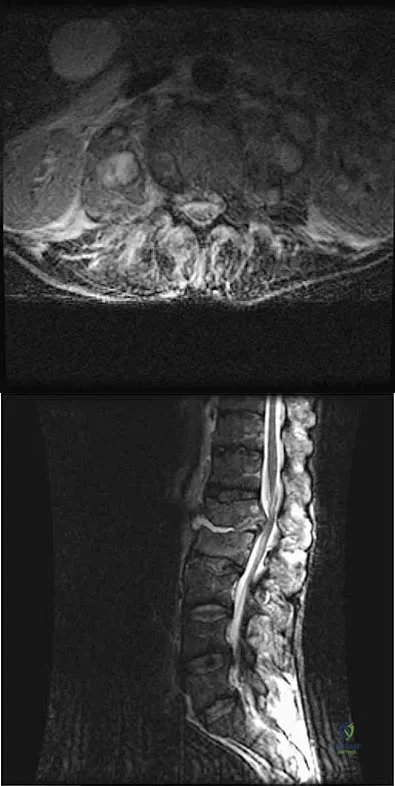

A 56-year-old man with a history of chronic lower back pain from lumbar spondylosis reports a 2-day history of acute incapacitating back pain. He denies any history of acute trauma, although he reports the pain starting after a coughing spell. He also reports difficulty urinating and some fecal incontinence. Examination reveals generalized lower extremity weakness, saddle paresthesia, hyporeflexia in the lower extremities, and loss of rectal tone. What is the most appropriate management at this time?

Correct Answer: Immediate MRI of the lumbar spine

Cauda equina syndrome is a medical emergency that must be quickly diagnosed and treated to avoid long-term complications. Cauda equina syndrome typically presents with low back pain, unilateral or usually bilateral sciatica, saddle sensory disturbances, bladder and bowel dysfunction, and variable lower extremity motor and sensory loss. Although a number of pathologies can cause cauda equina syndrome, in a patient with a history of chronic back pain, disk pathology is the most common cause of acute onset cauda equina syndrome. Whereas radiographs may be useful in a traumatic onset of symptoms, MRI is the most appropriate study. Cauda equina syndrome should be evaluated on an emergent basis and admission for work-up is appropriate. Ahn UM, Ahn NU, Buchowski JM, et al: Cauda equina syndrome secondary to lumbar disc herniation: A meta-analysis of surgical outcomes. Spine 2000;25:1515-1522.

Small SA, Perron AD, Brady WJ: Orthopedic pitfalls: Cauda equina syndrome. Am J Emerg Med 2005;23:159-163.